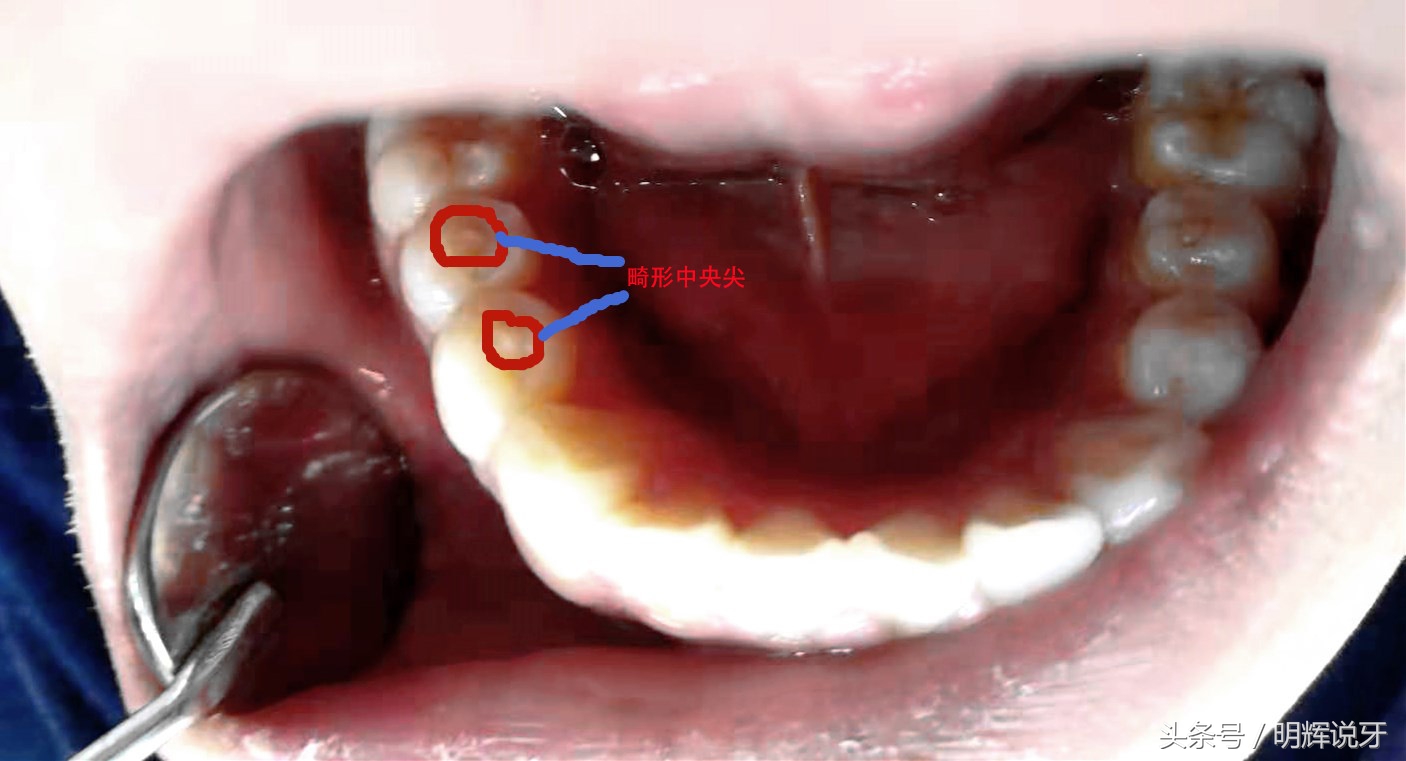

但是有些牙尖,让人烦恼,虽然你也不想见他,但是他确随你而来,你只能接受,因为他是天生的畸形,又称畸形中央尖,常见于前磨牙,突出在牙齿的最中间!

畸形中央尖